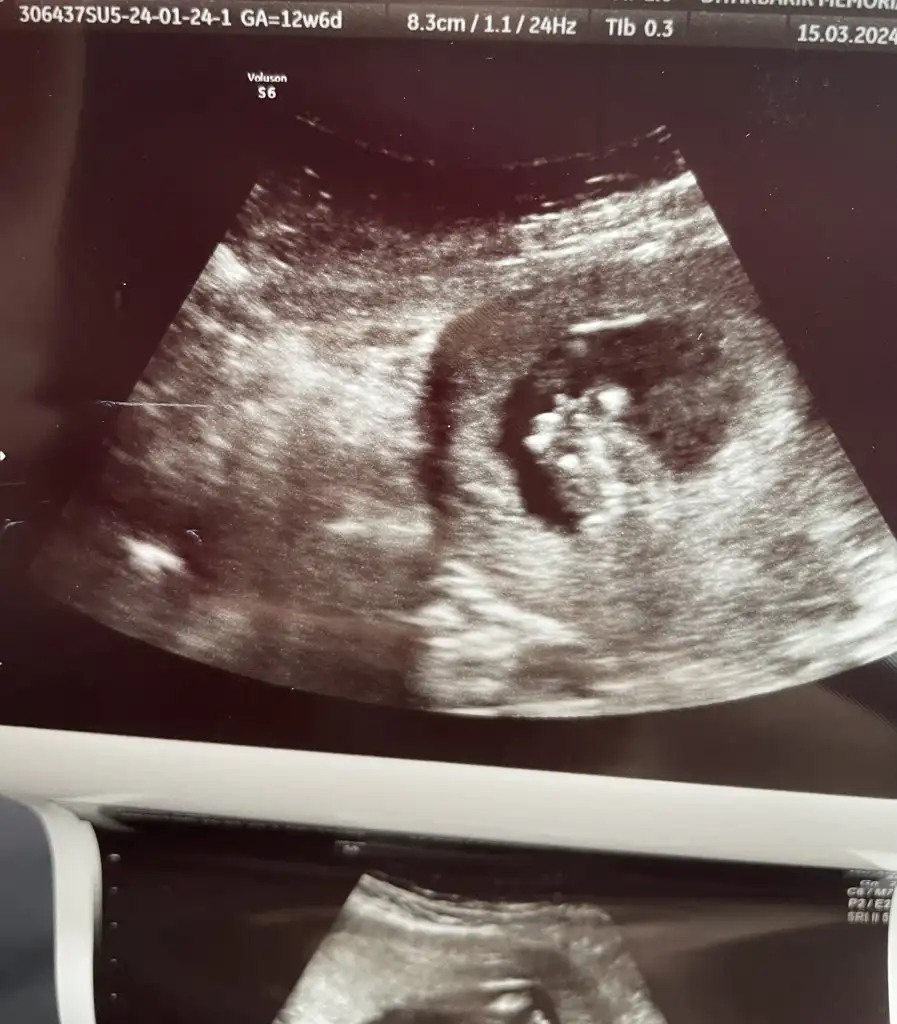

Banada pipiye benziyor dedi canım hatta iki bacak arası fotoğraf bile vermiş ben farketmedim bi arkadaş dedi pipi diye.@tali de erkek demişti.Bencr senin de öylr değişmezEki Görüntüle 3401677 Sağda ok işaretiyle gösterdi doktor erkek dedi ama kesin mi dedim 16. Haftaya kadar değişebilir ama şuan erkek benim fikrimce dedi

Öyle duruyor sağlıklı olsunlar da kız erkek fark etmez ama içimden kız hissediyordum tutmadıBanada pipiye benziyor dedi canım hatta iki bacak arası fotoğraf bile vermiş ben farketmedim bi arkadaş dedi pipi diye.@tali de erkek demişti.Bencr senin de öylr değişmez

Ben sana yazarım netleşsin canım aklımdasınCanım sanq ramse bakmışmıydık. 6 ile 10 hafta arası. Yorum yaptıklarım da genelde dönüş yapmıyor dedektif gibi eski mesajlara bakmaktan yoruldumyarın da benim bebişin cinsiyet için gidicez inşallah belli olur. Ben erkek tahmin ettim 6. Haftadan itibaren kendimin kine erkek diyorum bakalım ne çıkacak